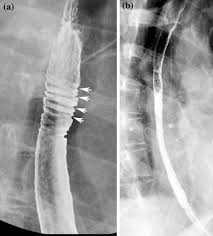

Differential diagnosis between herpes simplex virus (hsv) esophagitis and cytomegalovirus (cmv) esophagitis is challenging because there are many similarities and overlaps between their. Herpes esophagitis in healthy adults and adolescents: B from levine ms, woldenberg r, herlinger h, et al. Healing and relapse of severe peptic esophagitis after treatment with omeprazole. Candida and herpes simplex virus (hsv) esophagitis has been reported in 2% to 4% in immunocompromised patients.

Diseases Of The Upper Gi Tract Springerlink

Diseases Of The Upper Gi Tract Springerlink from media.springernature.com

Herpes esophagitis in otherwise healthy patients: Herpes esophagitis in healthy adults and adolescents: Infectious esophagitis (especially candida esophagitis) occasionally occurs in patients with diabetes mellitus or alcoholism, presumably because these diseases can impair immunity. Esophagitis may cause odynophagia and even esophageal hemorrhage, which is usually occult but can be massive. Hiv esophagitis is a possible cause of odynophagia in immunosuppressed patients with hiv. Behr j, kreuter m, hoeper mm, wirtz h, klotsche j, koschel d, andreas s, claussen m, grohé c, wilkens h, randerath w, skowasch d, meyer fj, kirschner j. We describe six cases to. Clinical guidelines of the russian gastroenterological association.